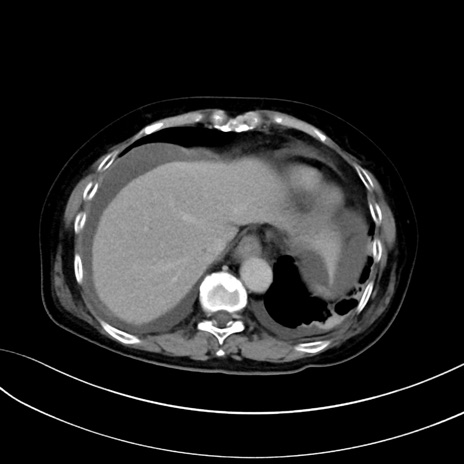

症例13 CT(横断像)1日半後